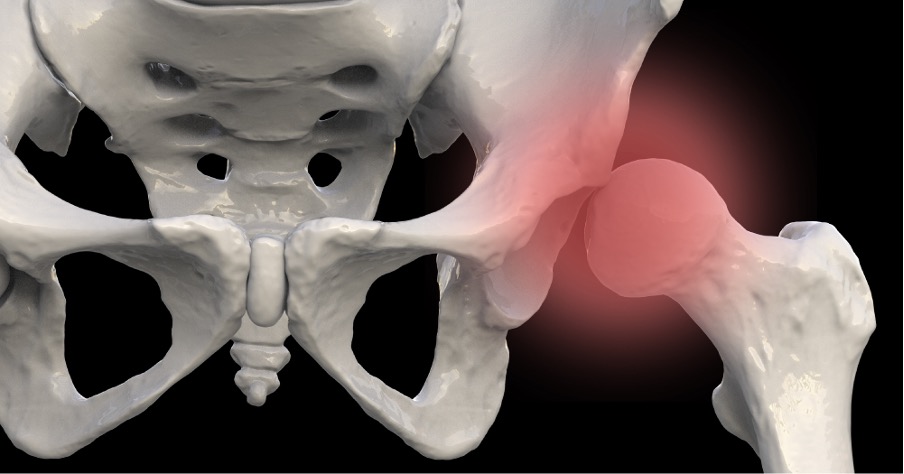

대퇴골두 골단 분리증

(SCFE)

대퇴골두 골단 분리증은 사춘기나 성장기 아이들에서 대퇴골두(허벅지뼈 머리 부분)의 골단(성장판 부위)이 대퇴 경부(대퇴골 목 부분)에서 미끄러지듯 분리되는 질환입니다. 쉽게 말해, 허벅지뼈 머리의 성장판 부위가 비정상적으로 움직여 탈구와 비슷한 상태가 되는 것입니다.